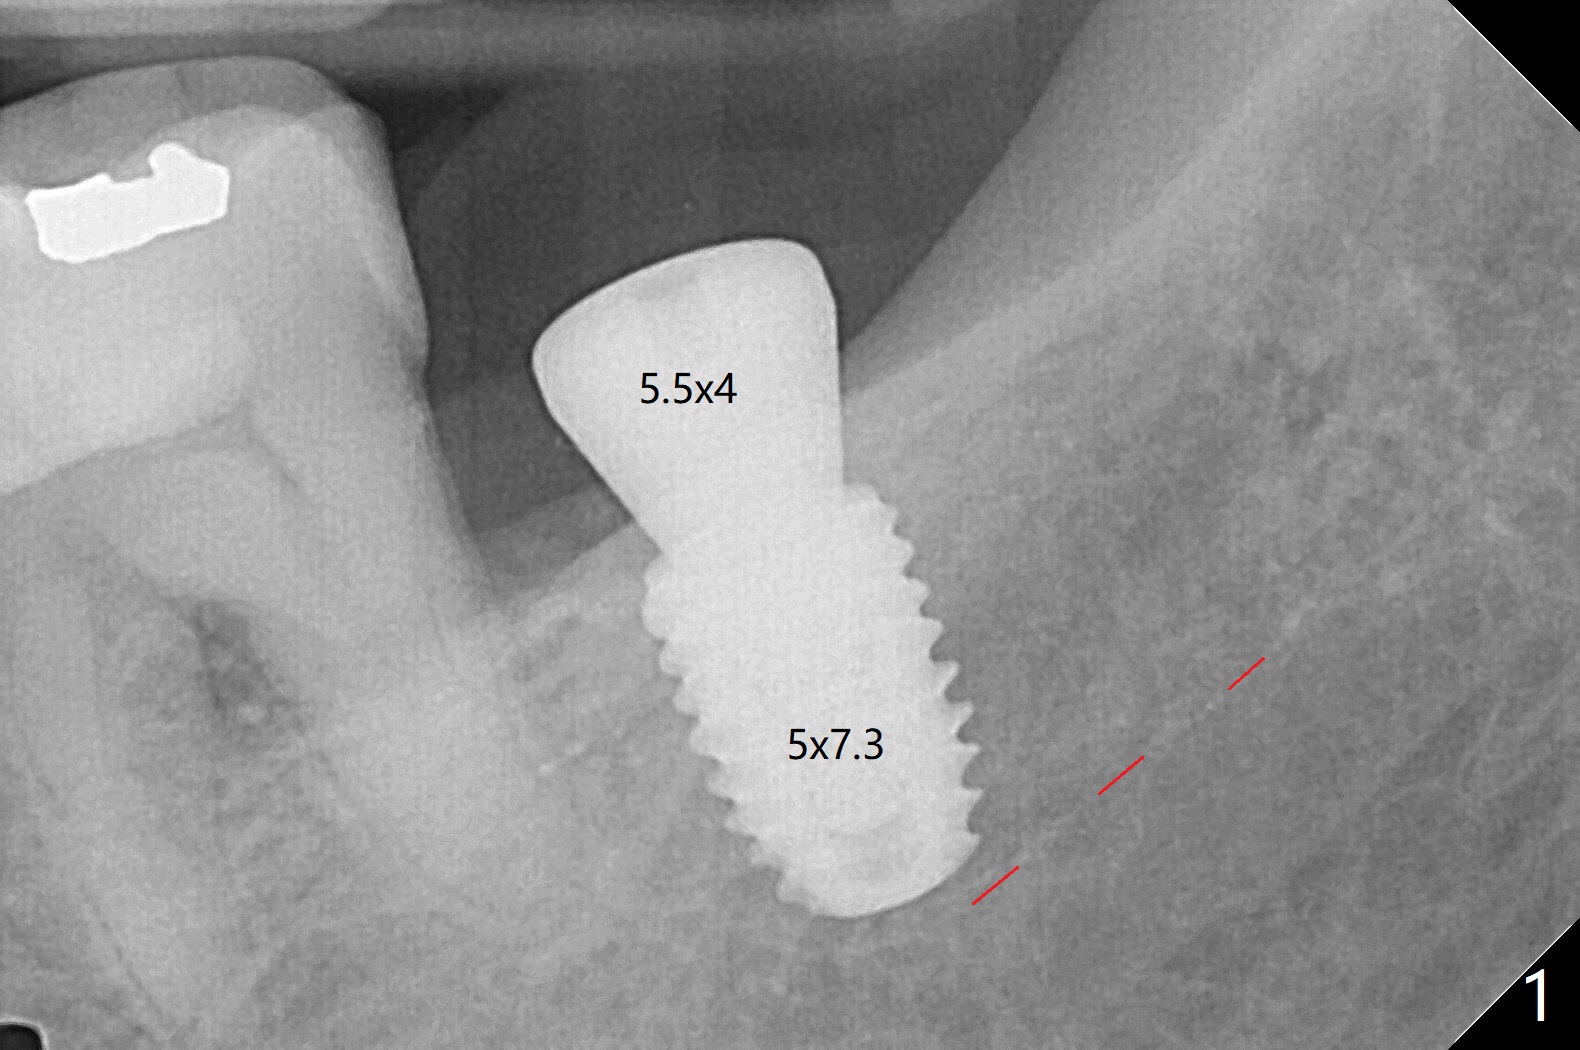

As expected, bone density is low at #31 during osteotomy. Underprep in depth (close to IAN) and diameter is done with satisfactory torque (~15 Ncm). What was not expected intraop is having to use one carpule of Septocaine in addition to Lidocaine. Postop PA shows why (closeness of the implant to IAN, Fig.1). The guide helps slightly subcrestal placement of the implant except lingual (equicrestal). Autogenous bone graft is placed, followed by sutures. Incision is initiated because of the narrow keratinized band. An IBS abutment seems to be completely seated in the IS implant (Fig.2). The gingiva is healthy at the time of impression.